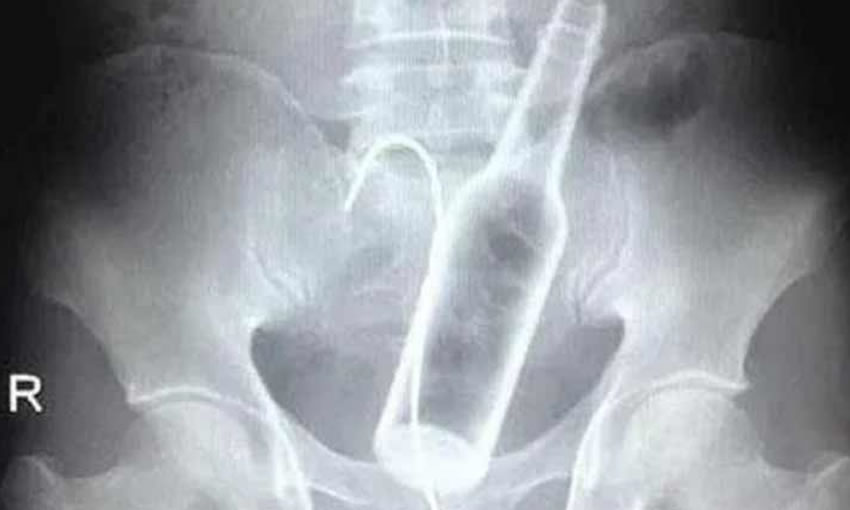

Após avaliação clínica, o rapaz foi submetido a uma cirurgia para remoção da garrafa.

Ainda não é possível afirmar qual é a extensão das lesões, e tampouco os danos que podem ter sido provocados por elas